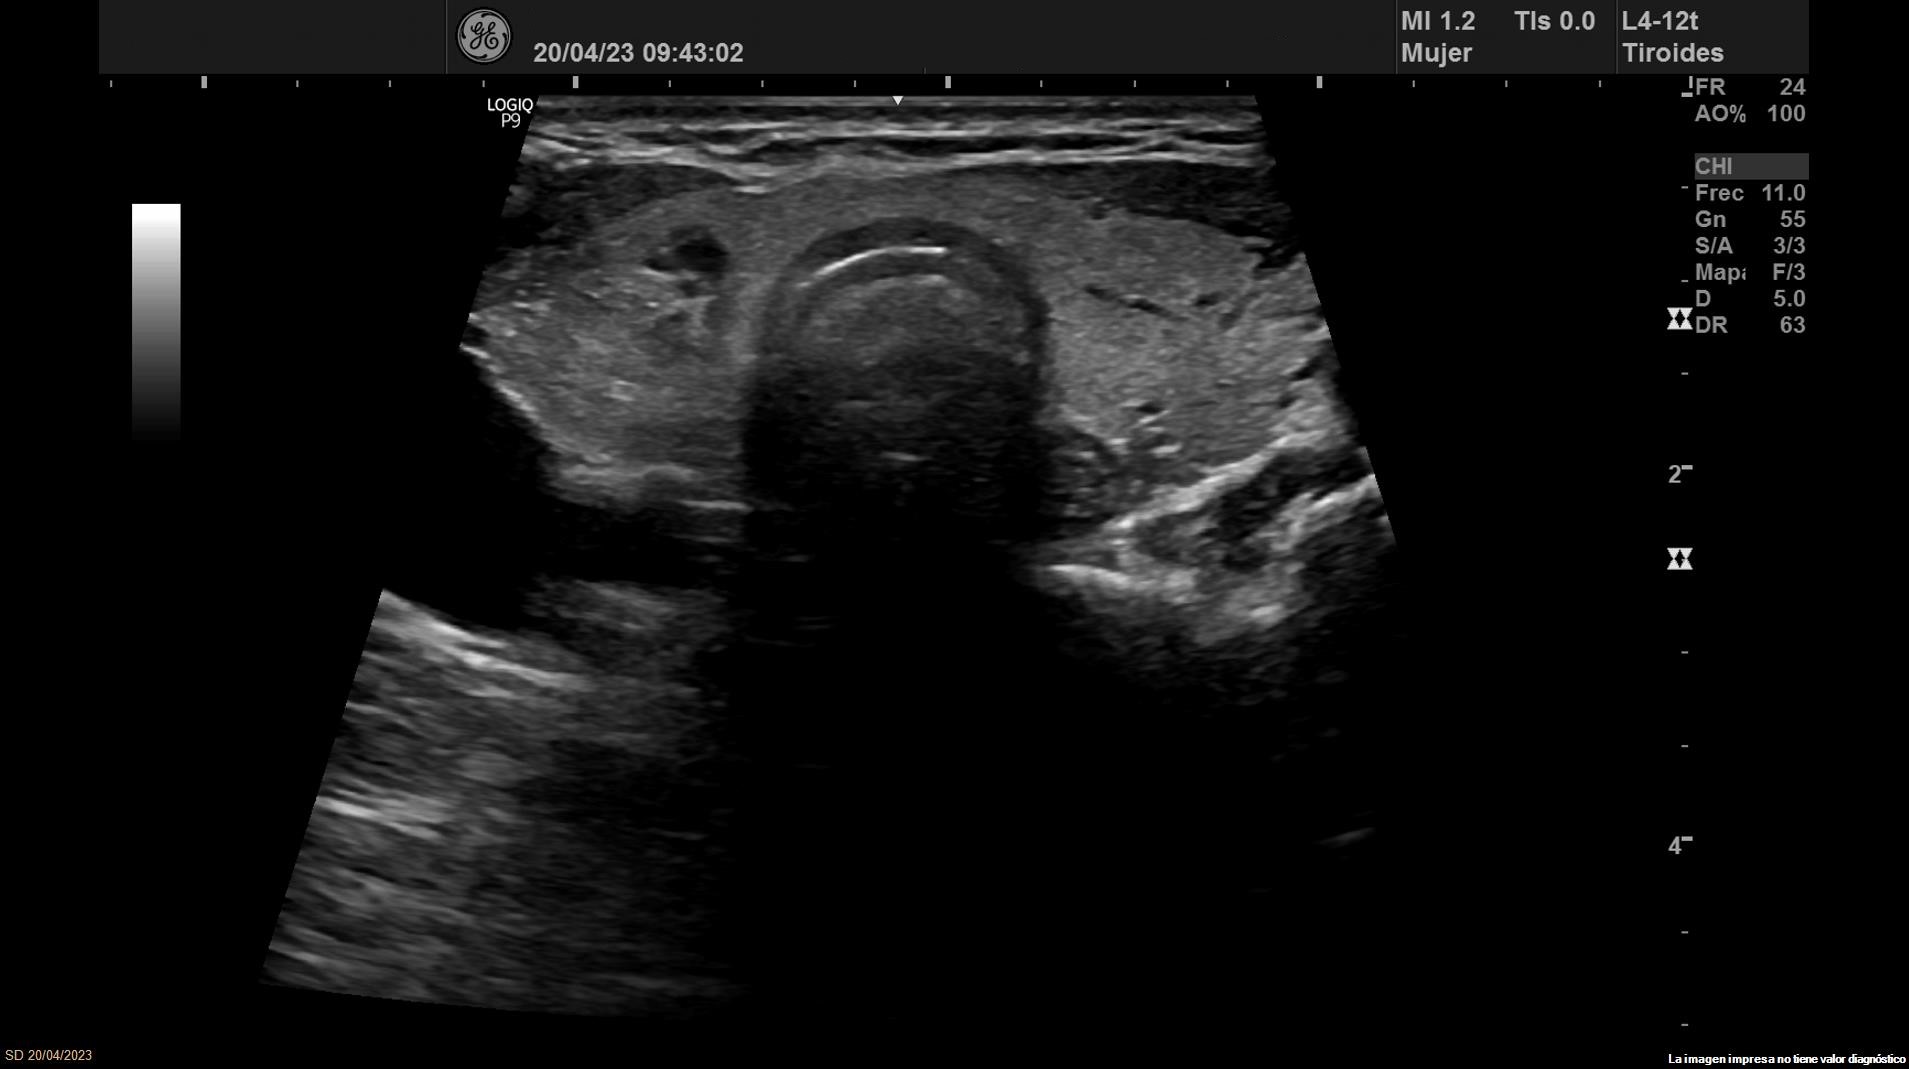

Se objetiva una adenopatía de 0,8 cm de aspecto benigno, ovalada y con bordes definidos. Además, se realiza ecografía tiroidea:

Ante los hallazgos obtenidos, nos planteamos el diagnostico diferencial entre los nódulos tiroideos benignos y malignos. Se deriva a Endocrinología donde realizan nueva ecografía que concuerda con la nuestra.